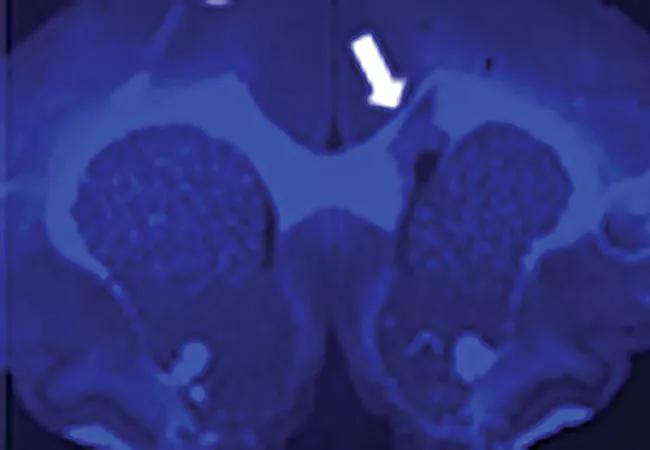

To assess its translational potential for use in humans, Myelivid underwent extensive preclinical testing.1,2 This included tests in experimental systems to demonstrate that the molecule specifically detected myelin in normal brain tissue and could sensitively demonstrate abnormal myelin changes as well (Figure 2).

Myelivid stains normal myelin and sensitively detects myelin lesions

Figure 2. Myelivid stains normal myelin and sensitively detects myelin lesions. Brain tissue specimens from a murine model were stained with Myelivid (A) and Luxol fast blue stain (B) and visualized with fluorescence microscopy (A) and light microscopy (B). The bright signal in panel A is due to intrinsic fluorescence properties of Myelivid. Stains were performed on adjacent slices of brain tissue obtained from the same subject. Arrows indicate the site of a myelin lesion, which is conspicuous due to decreased uptake of Myelivid and Luxol fast blue stain.